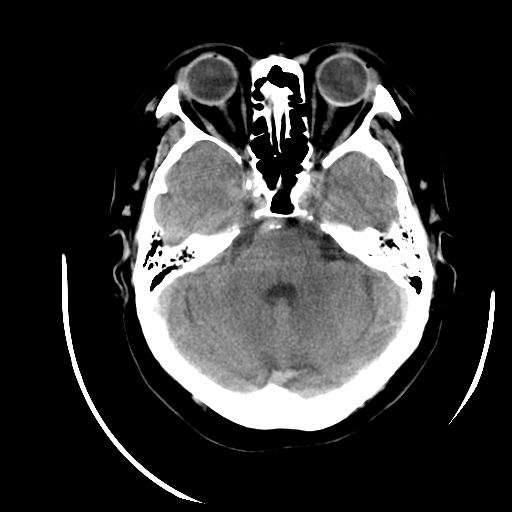

标题: CT16645:F70Y,头晕,头昬呕吐1天入院,右下肢肌力肌张力减底 [打印本页]

女70 头晕,头昬呕吐1天入院,右下肢肌力肌张力减底。高血压bp180/100

临床诊断:脑血管病1脑出血2脑梗塞

左侧内囊腔梗,脑底动脉硬化,多发钙斑形成,脑干梗塞可疑,空泡蝶鞍可疑

考虑左侧小脑梗塞。脑底动脉硬化

可疑脑干区腔梗,脑底多发动脉粥样硬化。

1)右侧额叶深部腔隙性脑梗塞。2)椎基底动脉迂曲、钙化。

右放射冠陈旧梗塞

椎基底动脉迂曲、钙化。右侧额叶腔隙性脑梗。